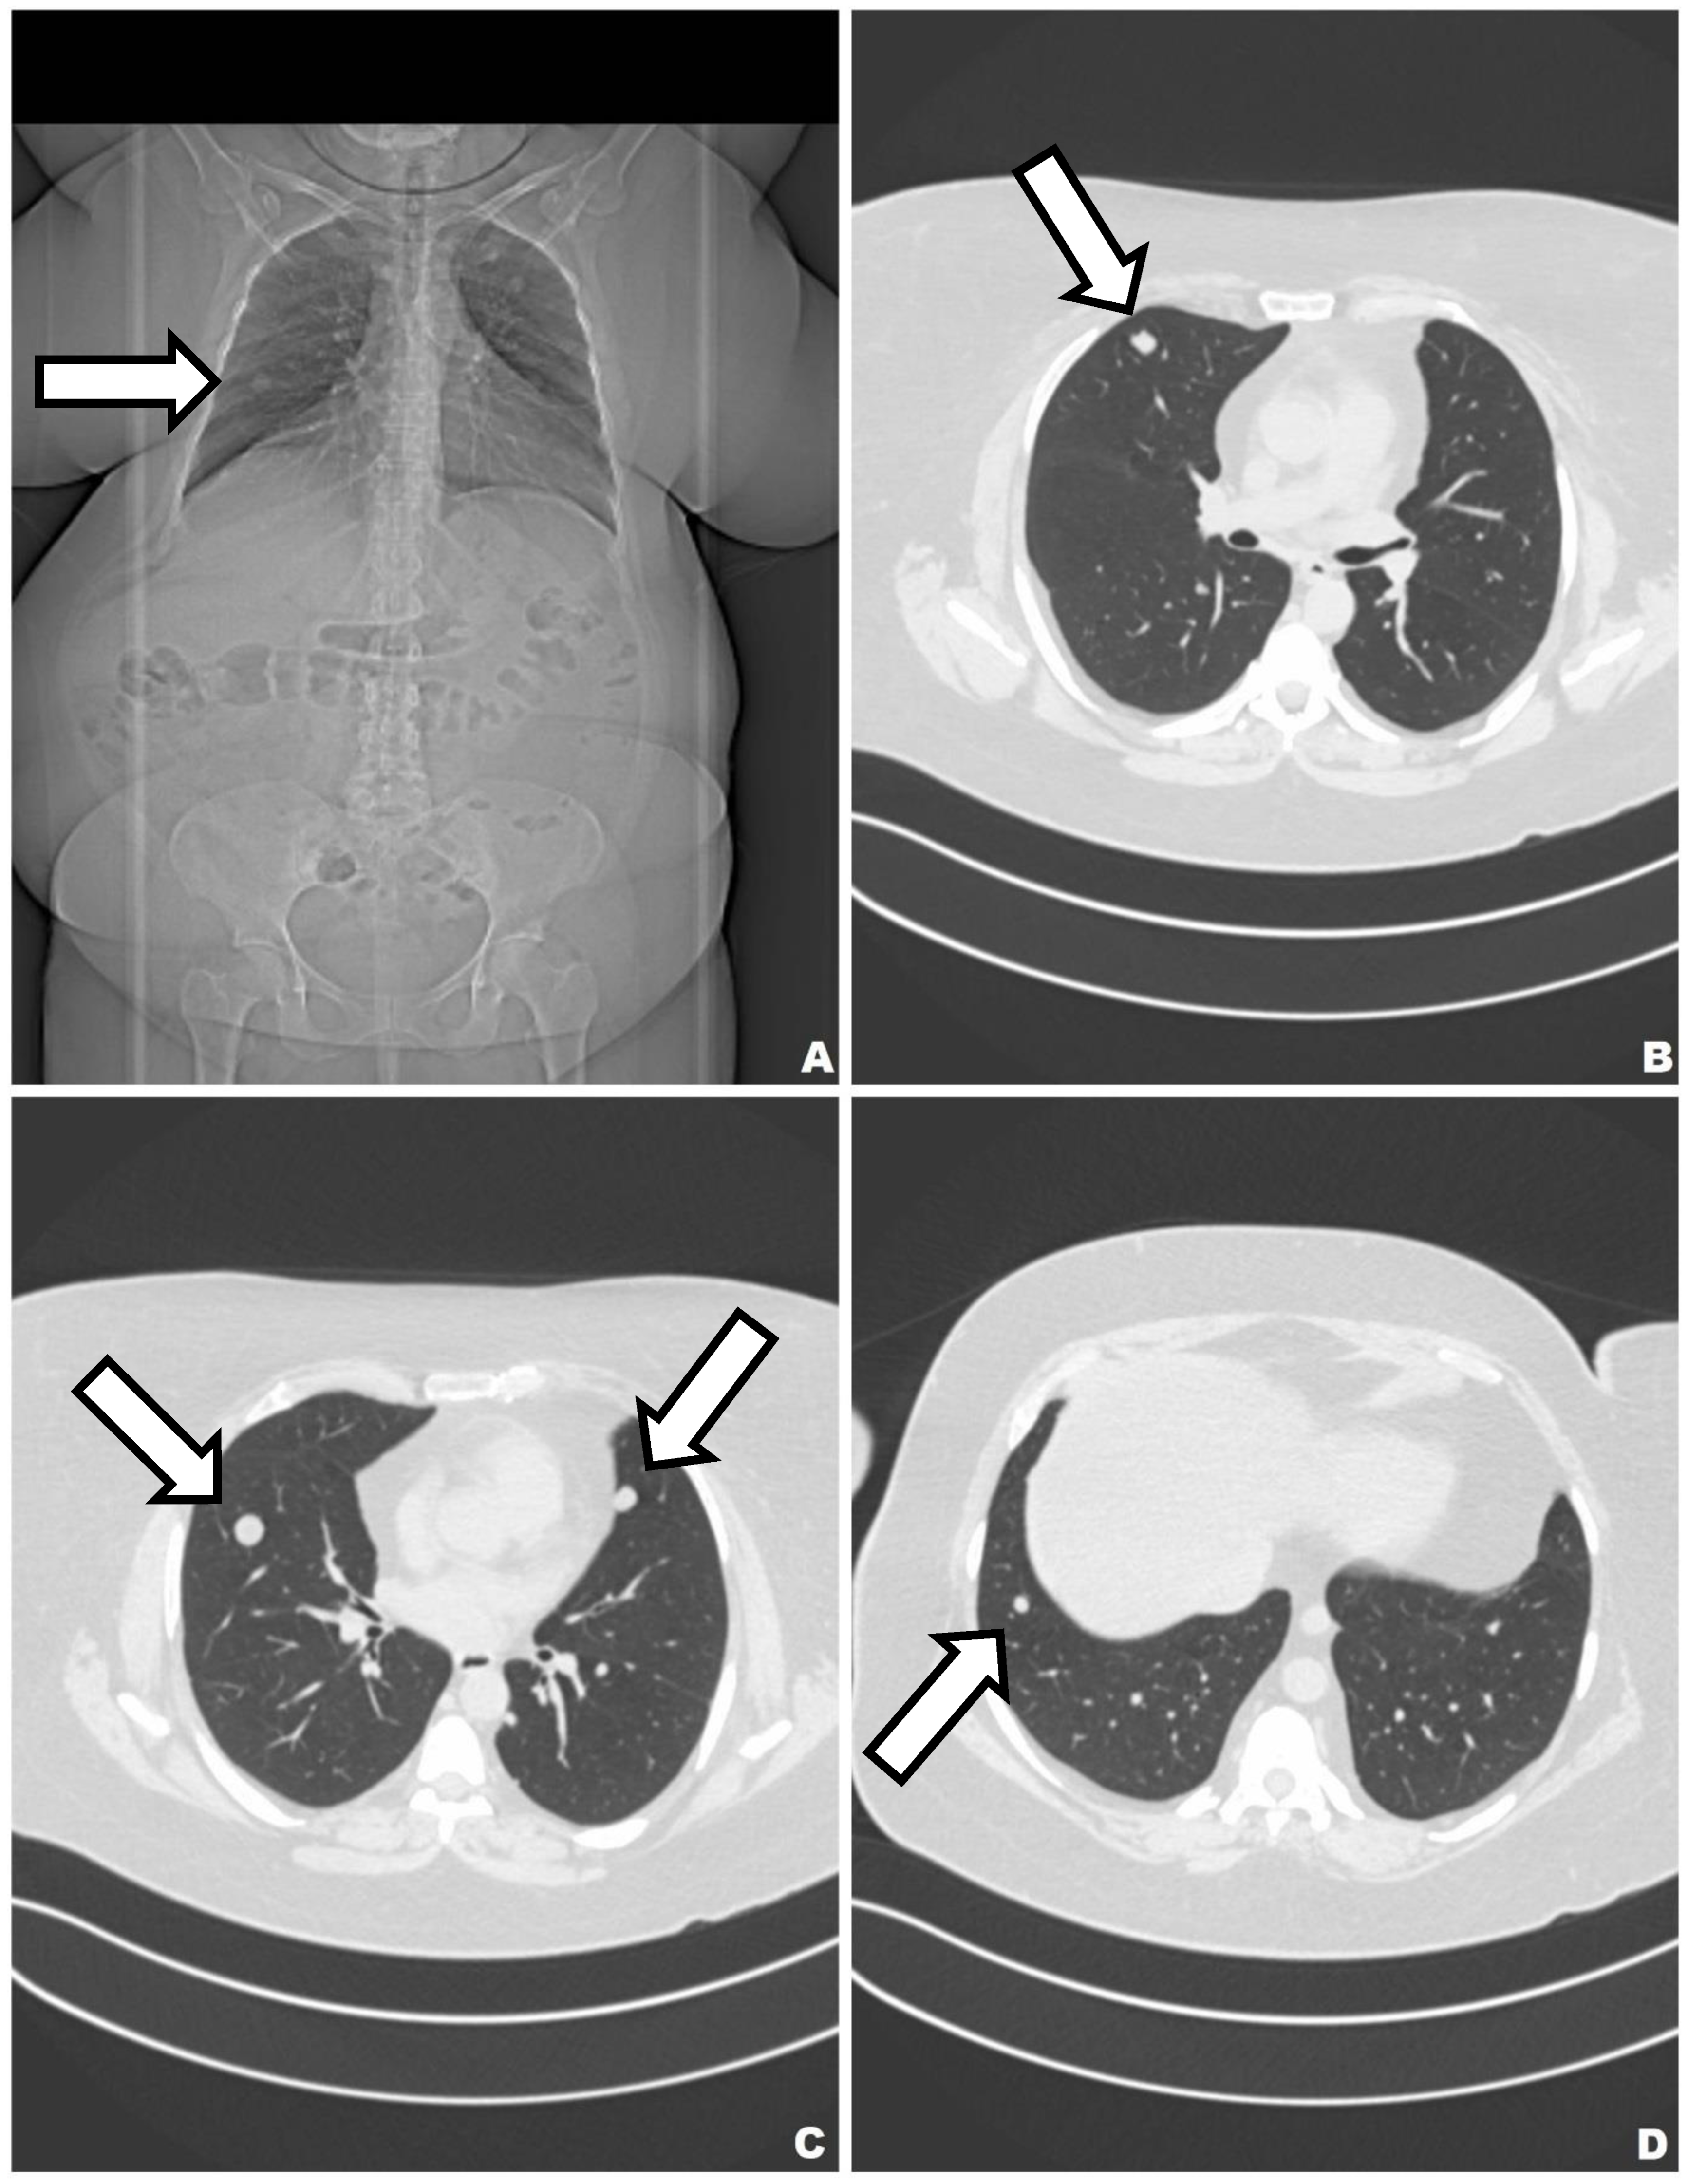

4. Case 3